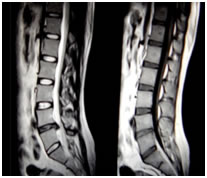

On lumbar MRI, overall prevalence of lumbar degenerative findings was disc bulge (figure 2) 125 (75.75%), nerve root compression 66 (40%), and central canal stenosis 44 (26.66%). The least common finding was disc herniation (figure 1) which was seen in 31 patients (18.78%) (Fig.1and2). Minority of participants 15 (9.09%) had normal lumbar MRI findings (Fig. 3).

Figure 2: Shows degeneration of lumbar intervertebral discs and at L4/L5disc herniation with sequestration and cord compression. Disc budges at L5/S1 level